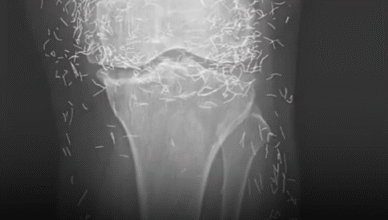

Новороздільська громада з глибоким сумом отримала звістку про непоправну втрату. Пішов із життя наш земляк, капітан медичної служби Олег Стефанович Костів. 30 вересня